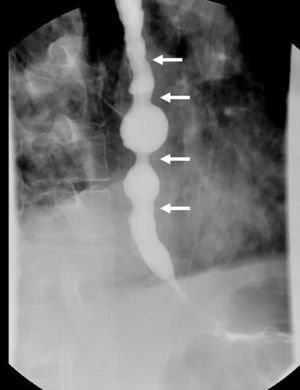

A 68-year-old man was evaluated in our clinic for intermittent dysphagia, regurgitation of liquids and solids, and chest pain. Esophagogastroduodenoscopy revealed a slightly dilated esophagus with retained food. Barium swallow showed esophageal indentations, with the characteristic “corkscrew” appearance (Fig. 1 arrows). High-resolution manometry confirmed the diagnosis of diffuse esophageal spasm (DES), with a hypertensive and non-relaxing lower esophageal sphincter. The ambulatory pH monitoring was normal. Because of the patient's progressive symptoms, which did not respond to calcium channel blocking agents and pneumatic dilatation, we performed a long laparoscopic Heller myotomy with Dor fundoplication (Fig. 2). Postoperative course was uneventful, and the patient was discharged after 24h on a soft diet. DES is a rare primary esophageal motility disorder characterized by dysphagia and intermittent chest pain. In these patients, the surgical myotomy should be extended more proximally than in patients with achalasia to obtain better relief of symptoms.